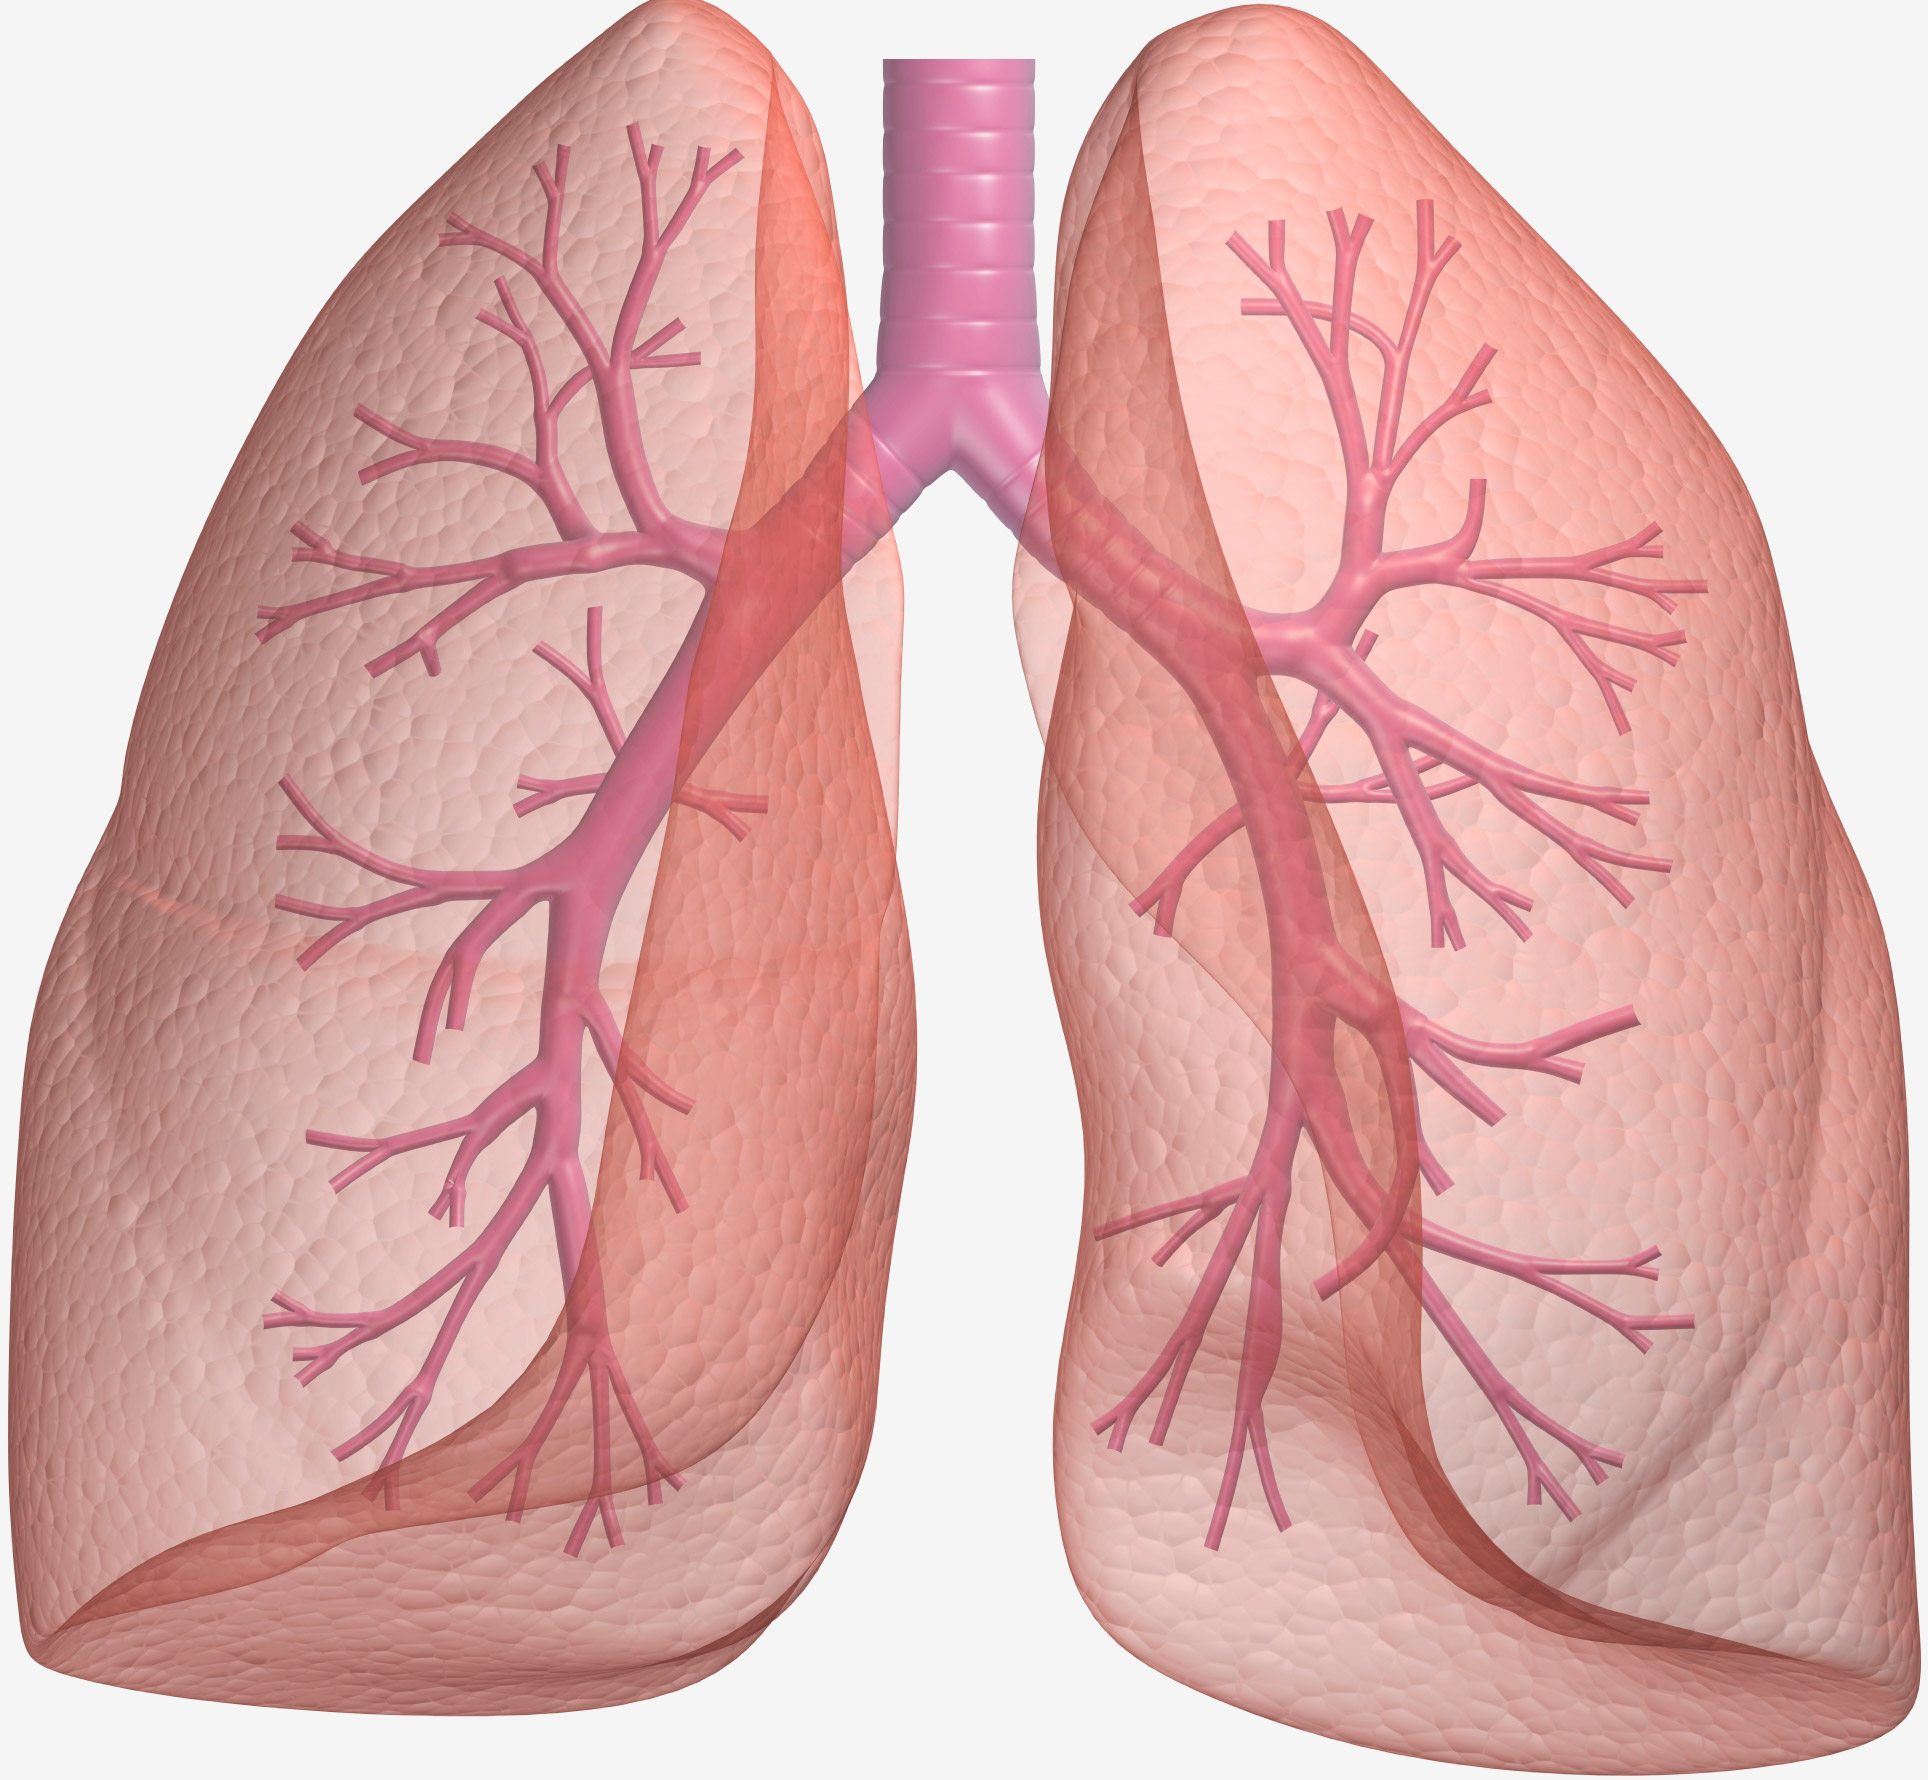

Здоровые Легкие Картинки

Здоровые Легкие Картинки 117 фото